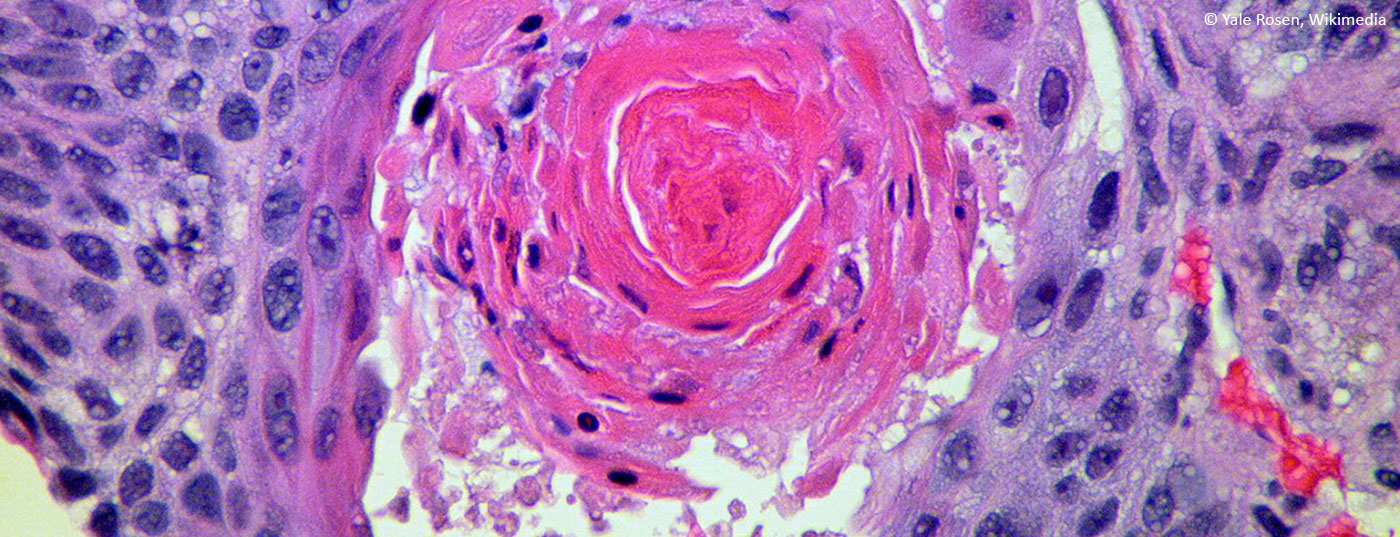

plattenepithelkarzinom_lungenkrebs

Aktuelle Systemtherapie beim metastasierten, nicht-kleinzelligen Bronchuskarzinom

Eine detaillierte molekulare Diagnose ist bei nicht-kleinzelligen ­Bronchuskarzinomen (NSCLC) heute obligat. Bei Vorliegen einer Driver-Mutation sollte wenn möglich der entsprechende Tyrosinkinase-Inhibitor in der ersten Linie eingesetzt werden. Bei Progression dieser Tumoren ist eine Rebiopsie sehr wichtig, um spezifisch angehbare Resistenzmechanismen zu erkennen. Bei NSCLC ohne Driver-Mutation ist als Erstlinienbehandlung die zyto­toxische Chemotherapie mit einem Platin immer noch Therapie der Wahl. In der Zweitlininentherapie ist die Immuntherapie den bisherigen Behandlungen eindeutig überlegen und darf als neuer Standard angesehen werden.